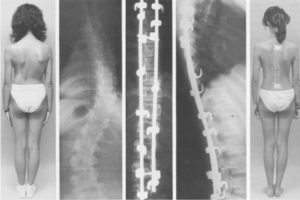

Применение дистрактора типа Харрингтона с боковой тягой

Для повышения эффективности использования дистрактора типа Харрингтона при оперативном лечении сколиоза некоторые авторы предлагают устанавливать дополнительную боковую тягу от дистрактора к вершине деформации позвоночника (Armstrong J., Connock I., 1975; Cotrel V., 1975; Slot G. et al» 1976).

Применяемая нами конструкция отличается от всех предложенных ранее — она надежна в работе и проста в установке.

Используемая приставка представляет собой толстостенную муфту, свободно передвигающуюся по стержню дистрактора.

Опорой для всей конструкции на позвоночник служит пластинка с отверстием в центре, через которое осуществляется тяга. Поперечно-экстензионная сила достигается с помощью гайки, навинчивающейся на винтовую нарезку тяги.

Техника установки включает в себя сборку конструкции. После соединения стержня дистрактора с крючками и проведения дистракции муфту перемещают к центру дуги искривления.

Тягу вводят в межостистуй промежуток, на нее надевают плоский длинный алло- или аутотрансплантат (резецированное ребро), через отверстие, просверленное в его центре, и поверх трансплантата надевают опорную пластинку.

Завинчивая гайку, плотно прижимают алло- или аутотрансплантат к остистым отросткам и осуществляют коррекцию деформации, одновременно применяя дистракционную силу. При резко выраженной патологической ротации боковую тягу следует осуществлять не за остистые отростки, а за поперечные отростки вершинных позвонков.

Представлено соотношение растягивающей и поперечно-экстензионной силы при различной выраженности дуги искривления. Как видно, деформации позвоночника, превышающие 90°, корригируются более эффективно при действии растягивающей силы. Использование поперечно-экстензионной силы сочетании с растягивающей показано в основном для коррекции кифосколиотических деформаций с дугой искривления 50-90°.

Применение боковой тяги дает возможность создать новую корригирующую силу, воздействующую на вершину искривления позвоночника, добиться динамической коррекции деформации (так как во время операции стержень дистрактора нагибается в сторону позвоночника, а в послеоперационном периоде выпрямляется, дополнительно уменьшая дугу искривления), сократить амплитуду колебаний самого стержня дистрактора за счет фиксации его середины, что уменьшает опасность перелома металлоконструкции, снизить величину потери коррекции в послеоперационном периоде, даже при смещении верхнего крючка. Чтобы предотвратить смещение последнего из-под суставного отростка, следует при использовании боковой тяги применять крючки с вилкообразными концами, которые захватывают корень дуги.